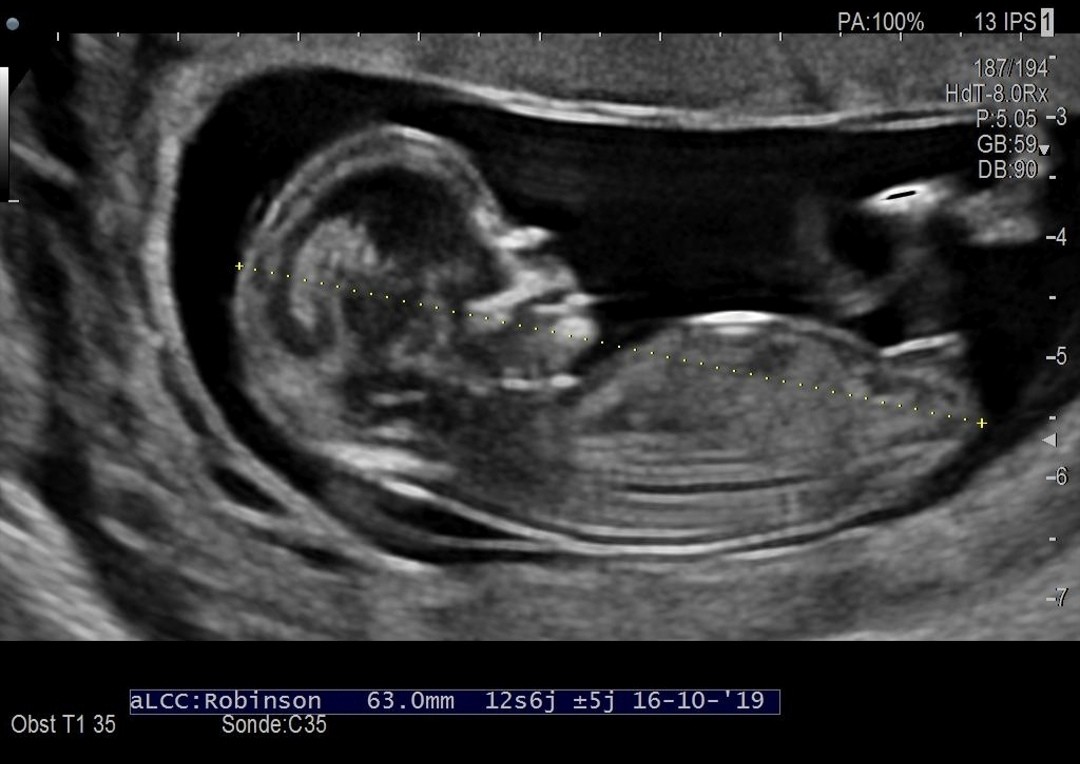

Maman d'une adolescente en pleine puberté, d'une petite puce de 5 ans et d'un petit bonhomme de 6 mois, je suis une vraie pile électrique Faut que ça bouge tout le temps !Vous devriez tout de même passer une autre échographie entre 18 et 22 semaines de grossesse afin de fournir encore plus de détails sur la morphologie de votre bébé La première échographie montrera également si vous attendez un bébé, des jumeaux ou plus Il est toujours utile de savoir, le plus tôt possible, s'il s'agit d Echo 12 SA 3 jours le 27/07 bébé mesure 63cm et son coeur bat à 153p/m 80% de chances que tu sois une petite princesse On t'aime !